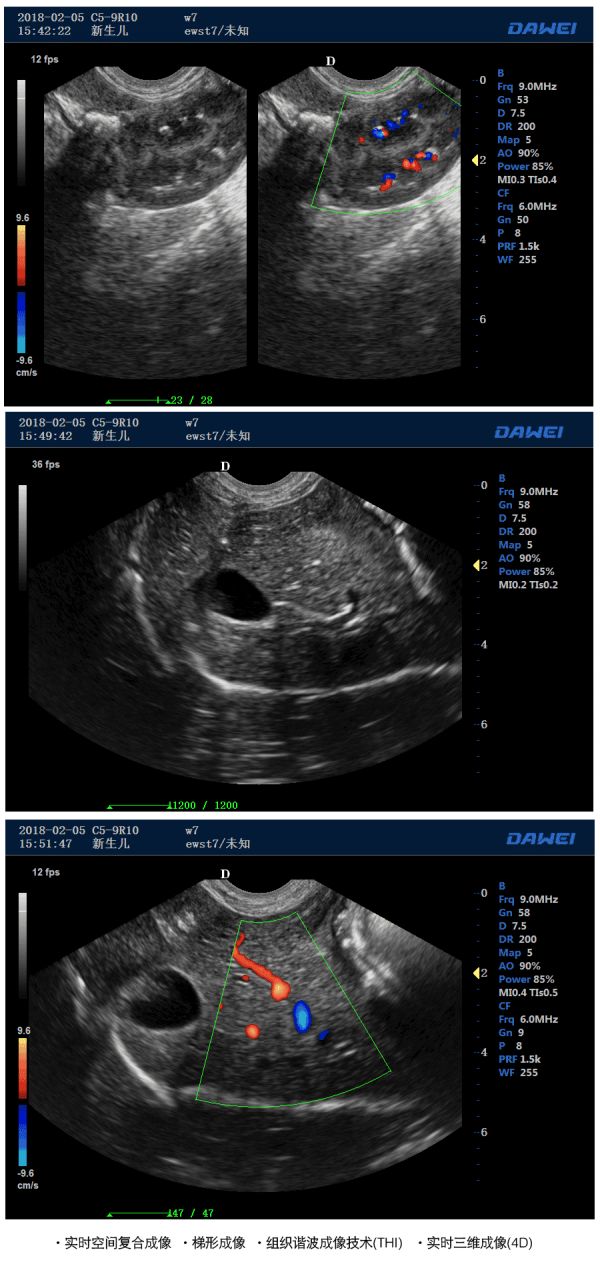

● 实时空间复合成像

● 梯形成像

● 组织谐波成像技术(THI)

● 实时三维成像(4D)